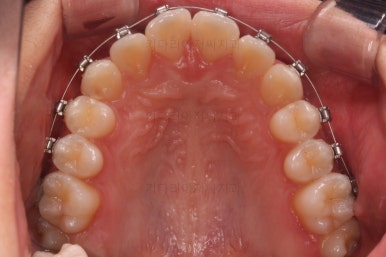

사용한 교정장치 : 자가결찰 메탈(엠파워 메탈, Empower metal) + 미니스크류

초진 시 다른 부위들 사진입니다.

약간의 주걱턱 느낌에 약간의 돌출감, 전반적인 치열의 가지런한 느낌은 나쁘지 않았지만 약간의 불량한 교합상태였어요.

다른 부분은 크게 바꾸지 말고 약간의 교합조절과 어금니 치료에 초점을 맞춰서 교정치료 계획을 잡았습니다.

이번에 사용한 장치는 엠파워메탈이라고 하는 자가결찰(철사를 잡아주는 뚜껑이 달려있는) 메탈(금속 성분) 장치였어요.

매우 장점이 많으나 심미성과 재료제작 비용 때문에 상대적으로 저렴한(이것도 장점일 수 있죠.) 장치입니다.

장치를 부착했을 때 입이 나오는 느낌, 웃을 때 느낌은 참고해 주세요.